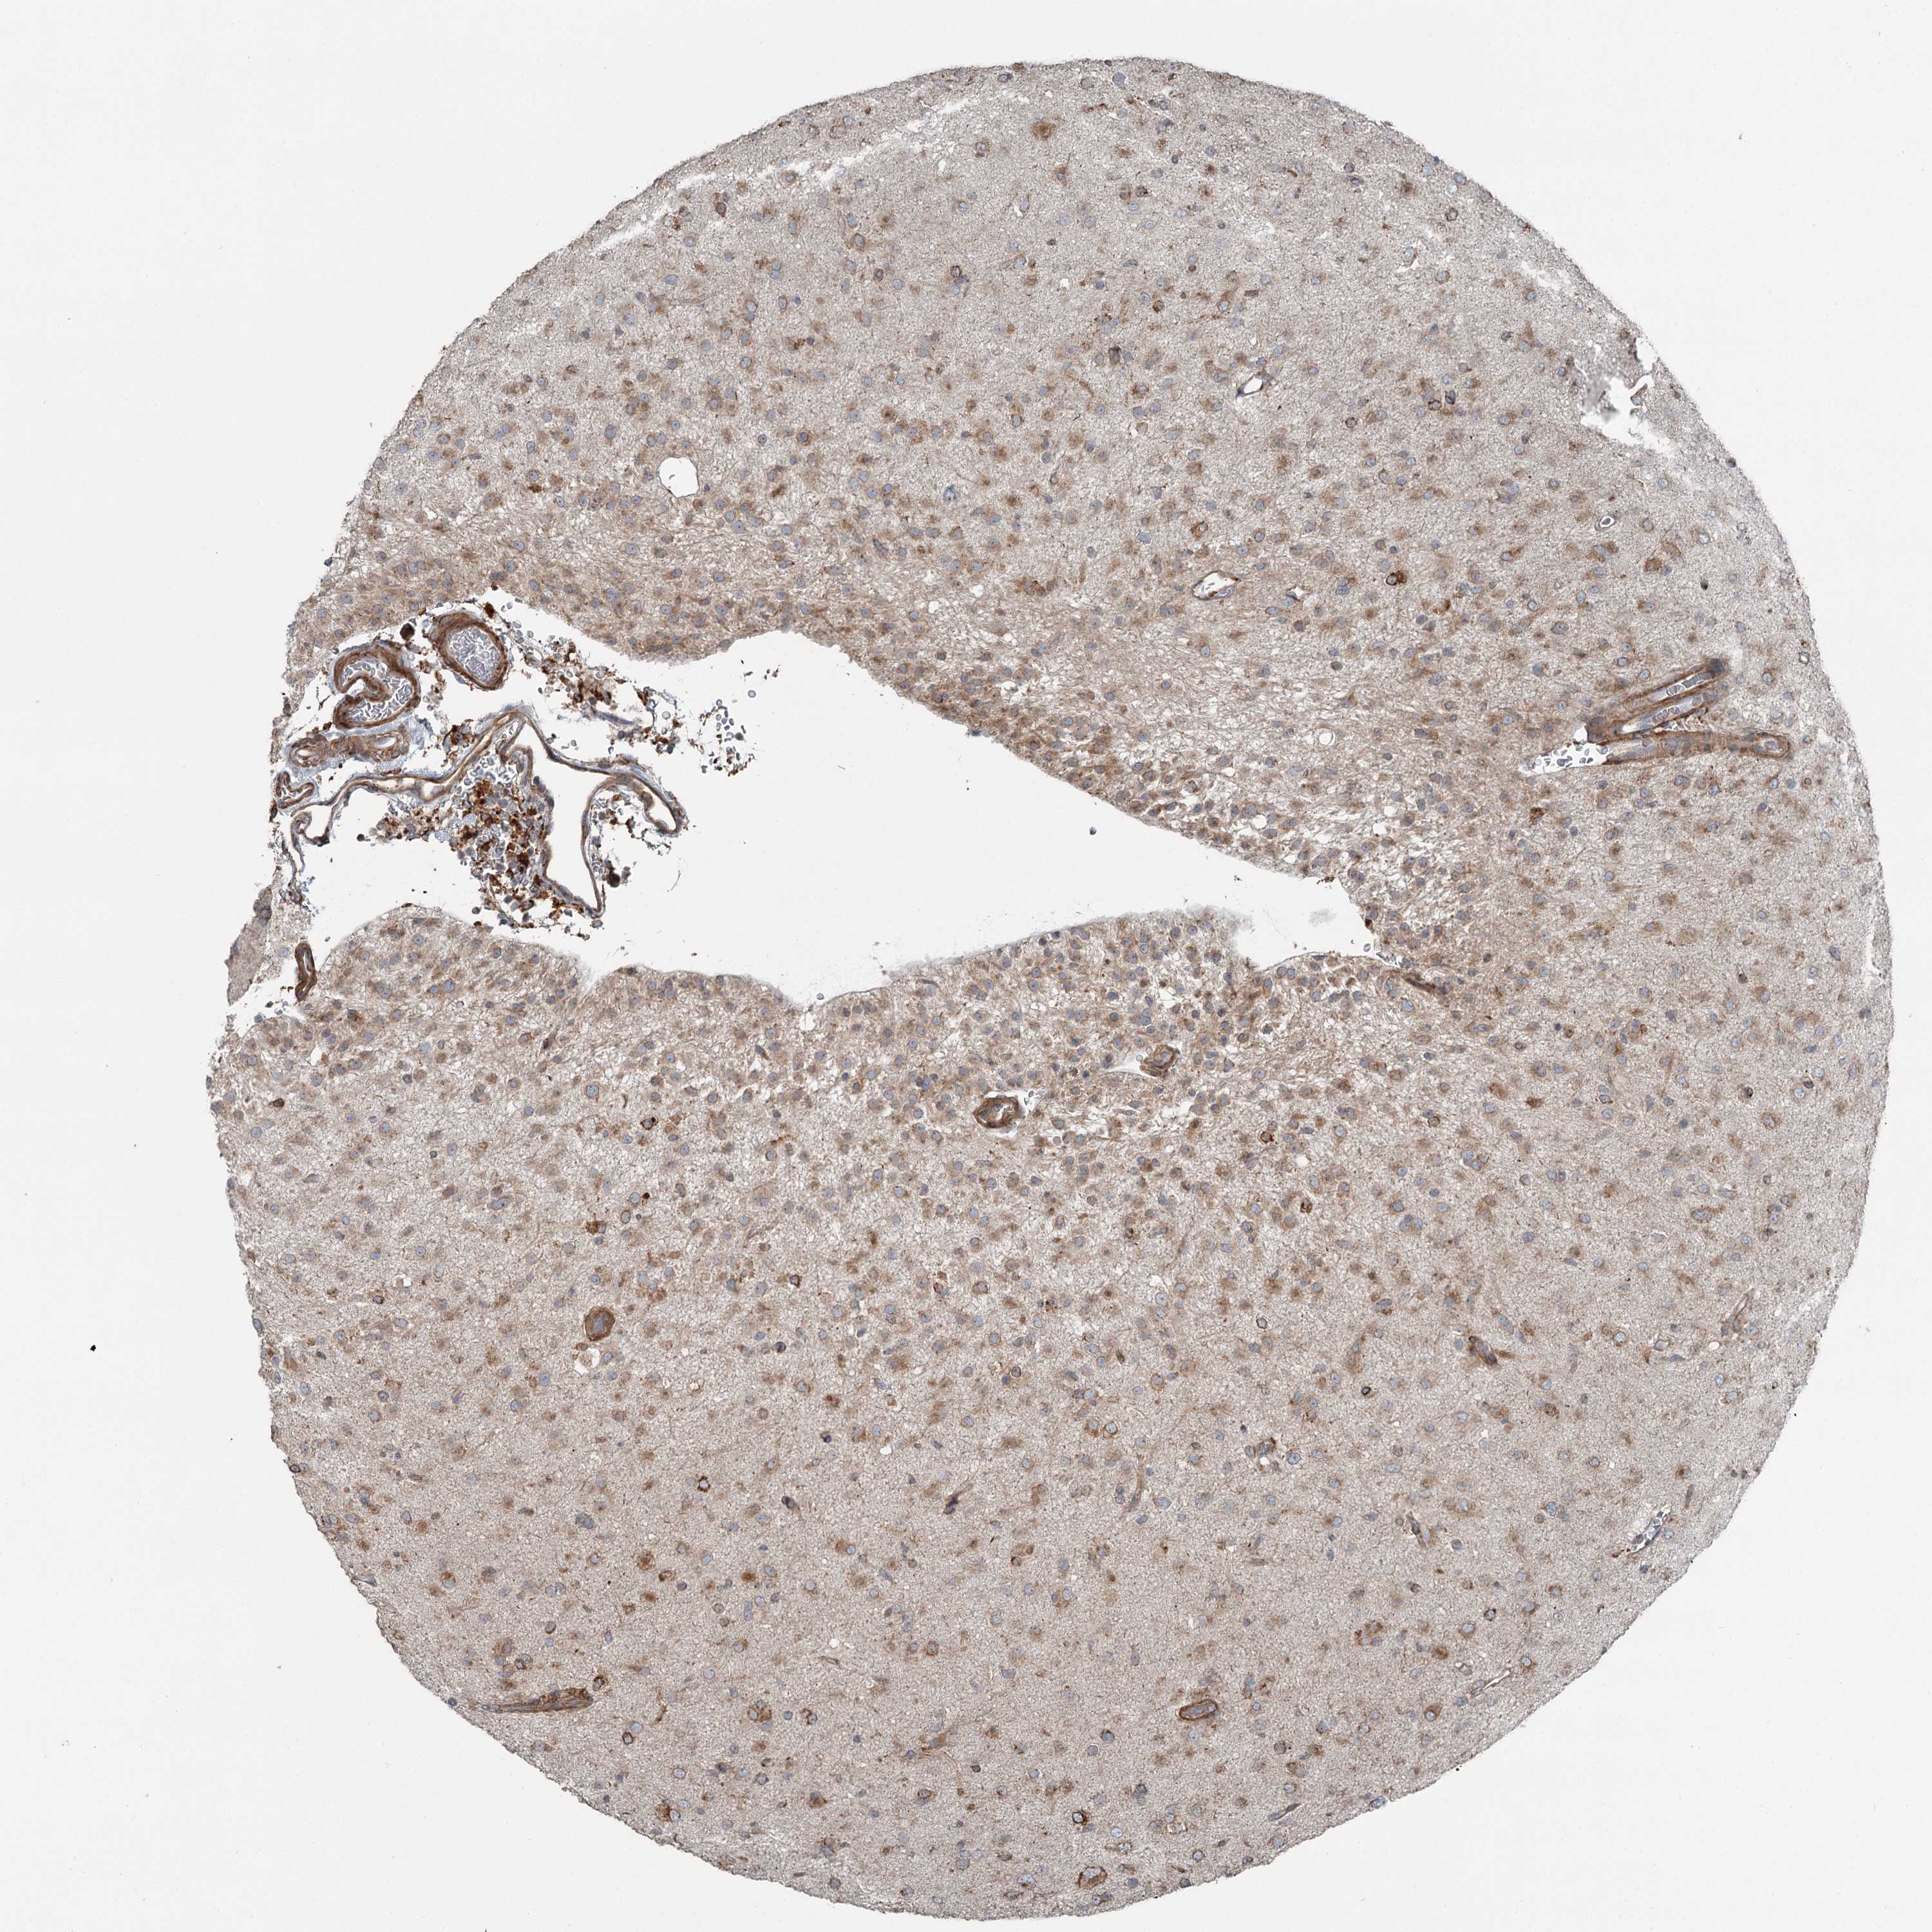

GLIOMA - Protein expressioni

A mouse-over function shows sample information and annotation data. Click on an image to view it in a full screen mode. Samples can be filtered based on level of antibody staining by selecting one or several of the following categories: high, medium, low and not detected. The assay and annotation is described here.

Note that samples used for immunohistochemistry by the Human Protein Atlas do not correspond to samples in the TCGA dataset.

Antibody stainingi

Antibody staining in the annotated cell types in the current human tissue is reported as not detected, low, medium, or high, based on conventional immunohistochemistry profiling in selected tissues. This score is based on the combination of the staining intensity and fraction of stained cells.

Each image is clickable and will lead to virtual microscopy that enables deeper exploration of all samples and also displays staining intensity scores, fraction scores and subcellular localization as well as patient and tissue information for each sample.

Antibody HPA038163

Antibody HPA038164

Staining

High

Medium

Low

Not detected

Intensity

Strong

Moderate

Weak

Negative

Quantity

>75%

75%-25%

<25%

None

Location

Nuclear

Cytoplasmic/membranous

Cytoplasmic/membranous,nuclear

Glioma, malignant, High grade

Glioma, malignant, Low grade

Glioblastoma, NOS